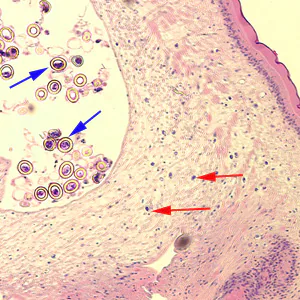

Microscopic identification of eggs and proglottids in feces is diagnostic for taeniasis, but is not possible during the first 3 months following infection, prior to development of adult tapeworms. Repeated examination and concentration techniques will increase the likelihood of detecting light infections. Nevertheless, identification of Taenia is not possible if solely based on microscopic examination of eggs, because all Taenia species produce eggs that are morphologically identical. Eggs of Taenia spp. are also indistinguishable from those produced by cestodes of the genus Echinococcus (tapeworms of dogs and other canid hosts). Microscopic identification of gravid proglottids (or, more rarely, examination of the scolex) allows species determination.

Separation of T. saginata and T. solium is best accomplished by examination of mature proglottids. Taenia saginata has 12-30 primary lateral uterine branches, while T. solium has 7-13 primary lateral uterine branches. Visualization of the branches can be improved by clearing the specimen in lactophenol followed by India ink injection into the lateral genital pore. The procedure is as follows:

Figure B: Mature proglottid of T. saginata, stained with India ink. Note the number of primary uterine branches (>12). Image courtesy of the Orange County Public Health Laboratory, Santa Ana, CA.